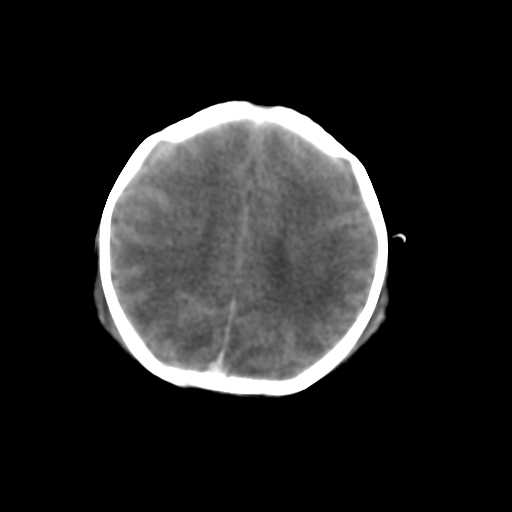

新生儿女2天,有窒息史,经抢救好转!白质最低ct值>23hu,请教各位老师:是否有出血?是否合并缺氧脑病?谢谢!

hie、蛛网膜下腔出血,皮下血舯。

双侧额叶白质低,白质ct值低于18hu可以考虑水肿改变

后纵裂密度高,前纵裂密度低,比较来说应该考虑有蛛网膜下腔出血

空三角征,蛛网膜下腔出血。